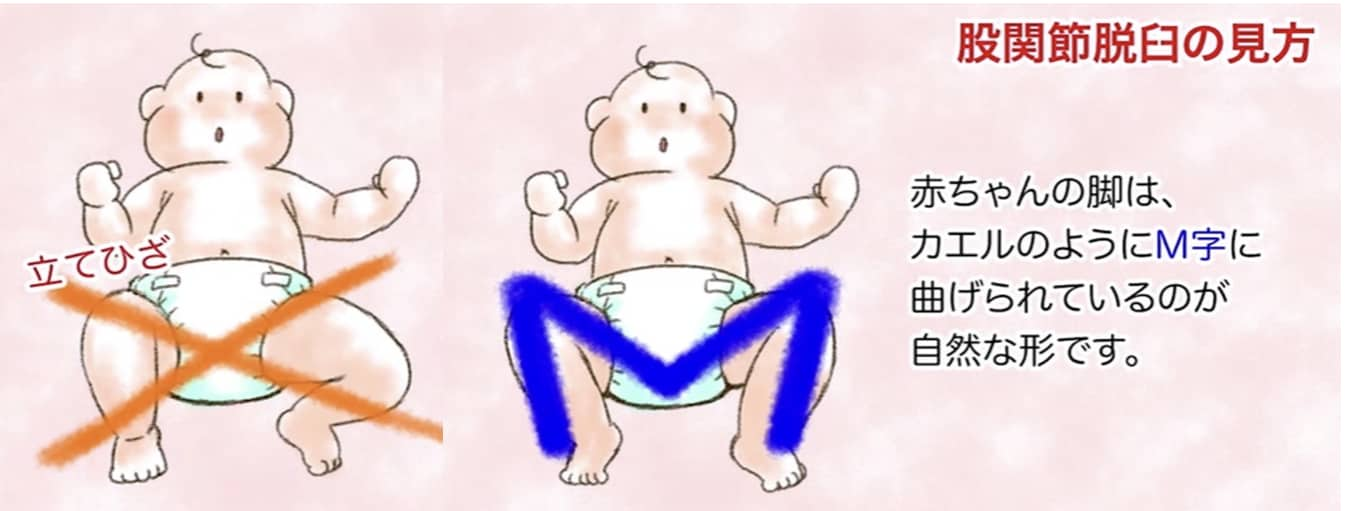

② 脚の開き(開排制限)

股関節の開きにくさ(開排制限)を調べます。両膝を合わせた状態からゆっくり開いていきます。女児 80度、男児 70度以上開くのが正常です。開きが悪いときには脱臼の可能性があります。女児は関節が柔らかいので脱臼があっても開排制限がないこともあります。

股関節の開きにくさ(開排制限)を調べます。両膝を合わせた状態からゆっくり開いていきます。女児 80度、男児 70度以上開くのが正常です。開きが悪いときには脱臼の可能性があります。女児は関節が柔らかいので脱臼があっても開排制限がないこともあります。

① おむつ

三角/巻おむつではなく股おむつを使って、脚が自由に動かせるようにしましょう。M字型に開けるようにして、伸ばされた状態で固定しないようにしましょう。股関節を開くために、二重おむつで無理やり開いて固定するのは逆効果です。

三角/巻おむつではなく股おむつを使って、脚が自由に動かせるようにしましょう。M字型に開けるようにして、伸ばされた状態で固定しないようにしましょう。股関節を開くために、二重おむつで無理やり開いて固定するのは逆効果です。